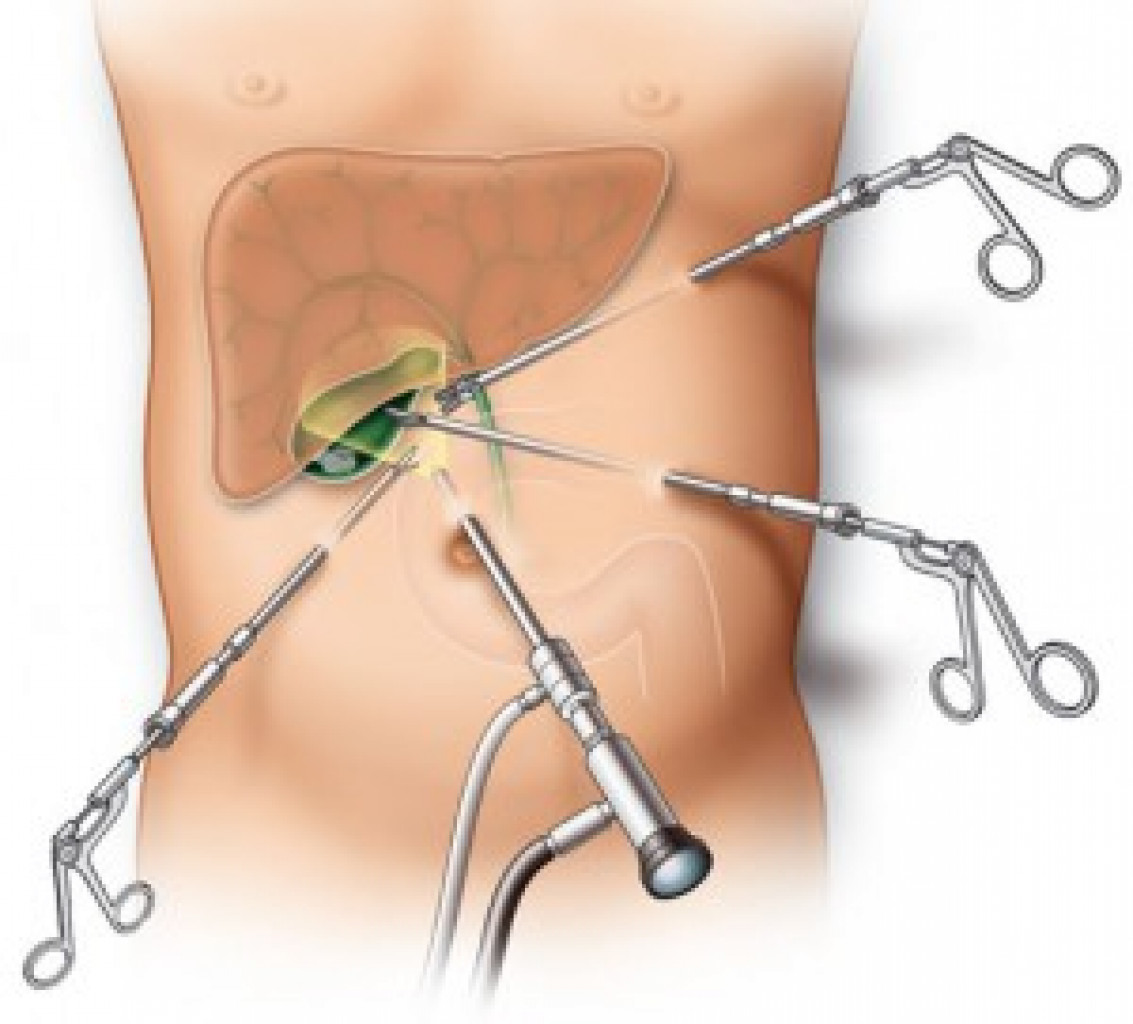

Современные методы лапаротомии и миомэктомии